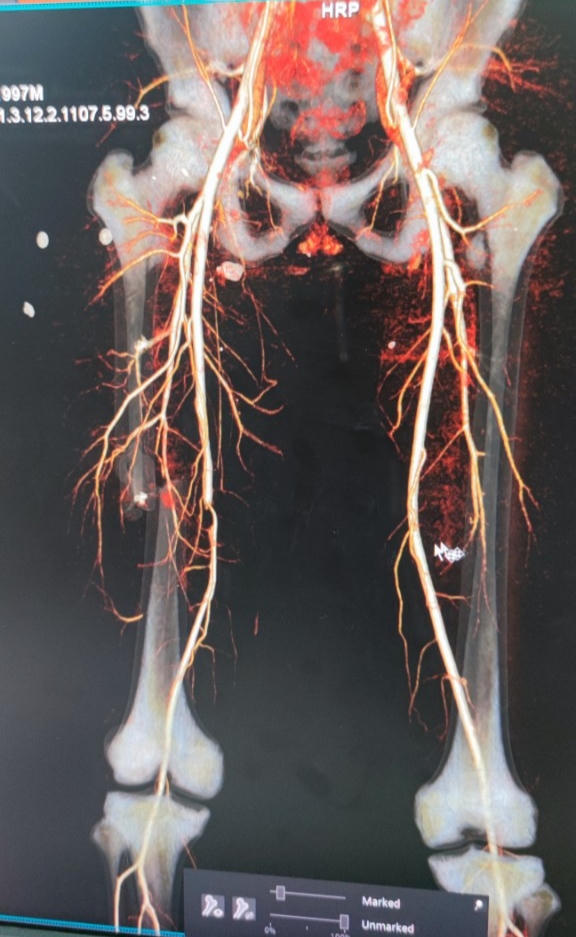

Ngày 10/4, Nguyễn Ngọc Th. (SN 1997, trú tại huyện Bố Trạch, tỉnh Quảng Bình) nhập viện cấp cứu trong tình trạng đa chấn thương do bị ô tô đâm, với các biểu hiện như: phần đùi phải bị sưng nhẹ, biến dạng; động mạch chày trước và chày sau chân phải không bắt được…

Xương đùi của bệnh nhân Th. bị gãy và động mạch đùi bị đụng dập, huyết khối gây tắc. |

Các bác sĩ đã nhanh chóng chẩn đoán, xác định bệnh nhân bị gãy kín 1/3 vùng giữa xương đùi phải và bị tổn thương đụng dập động mạch đùi, huyết khối gây tắc động

Bệnh nhân Th. đã được thực hiện phẫu thuật kịp thời để cắt bỏ đoạn động mạch đùi bị đụng dập, lấy bỏ huyết khối, ghép nối động mạch đùi, tái tạo lưu thông máu chân phải và kết hợp xương đùi phải bằng nẹp vít khoá.